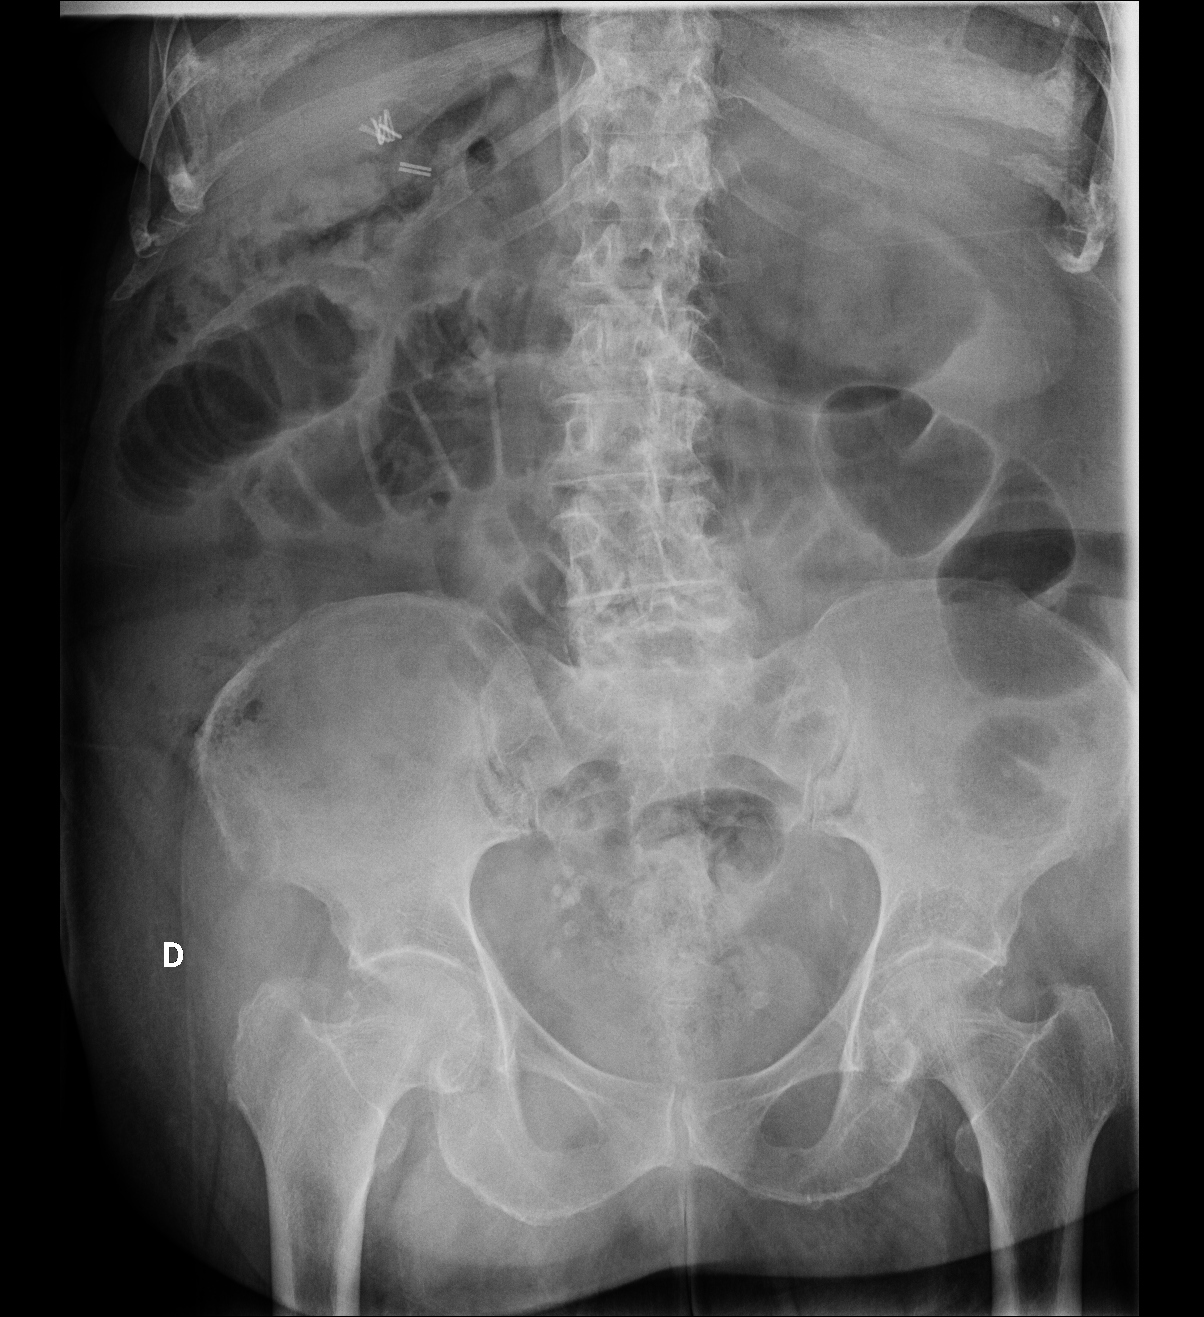

Rx en decúbito supino y en bipedestación